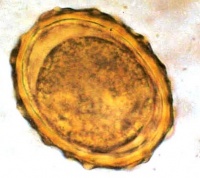

从人体排出的蛔虫卵有受精卵和未受精卵两种。受精卵呈宽椭圆形,大小45~75×35~50μm,卵壳厚而透明,卵壳外有一层凹凸不平的蛋白质膜,系由虫体子宫分泌并附着于虫卵,被胆汁染成棕黄色。卵内含一个大而圆的卵细胞,在卵细胞和卵壳的两端有新月状空隙。未受精卵呈狭长的椭圆形,约88~94×39~44μm,卵壳和蛋白质膜均较薄,卵内含大小不等的屈光颗粒。若蛔虫卵的蛋白质膜脱落,卵壳则无色透明,表面光滑,应注意与钩虫卵的鉴别。

蛔虫虫卵